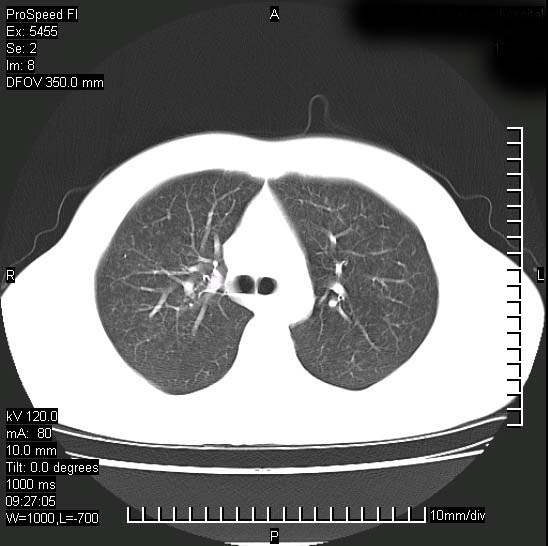

以下是引用zjzjr在2008-12-3 20:50:00的发言:[br]考虑泛细支气管肺炎,建议进一步检查除外肺出血性疾病如含铁血黄素沉着症、肺肾综合征等。

以下是引用zjzjr在2008-12-3 20:50:00的发言:[br]考虑泛细支气管肺炎,建议进一步检查除外肺出血性疾病如含铁血黄素沉着症、肺肾综合征等。

以下是引用光线在2008-12-3 20:19:00的发言:[br]双肺间质性改变。